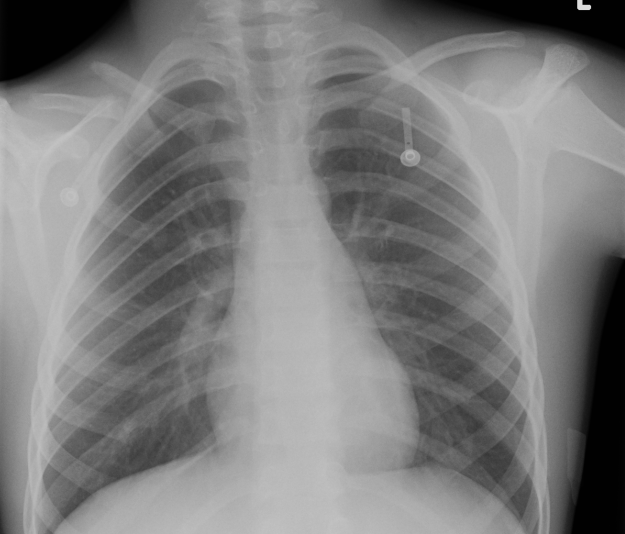

X-ray

Bulbous ends overlying each other